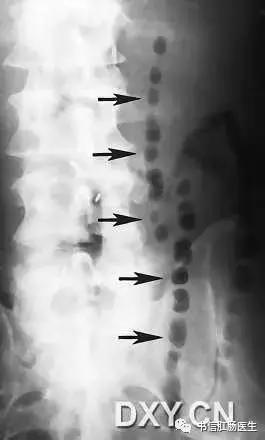

★ 图示小肠梗阻患者,左侧卧位。气泡(箭头)为环状皱壁间的气体潴留。

■ 影像表现:珠链征可见于小肠梗阻患者的立位或侧卧位腹部 X 线平片,由一些斜行或水平走向的小气泡排列构成,形似一串珍珠,因此称为珠链征。

■ 征象解析:串状排列的气泡代表显著扩张的积液的小肠闭襻内嵌在黏膜皱壁之间的气体影,X 线摄影的半月效应使被液体围绕的气泡呈卵圆形或圆形。珠链征的形成取决于气体积液的小肠襻和小肠蠕动亢进同时并存。

■ 讨论:肠梗阻是一种常见的外科急腹症。X 线平片对梗阻的存在、性质、部位、程度及可能原因的诊断有一定帮助。无论什么性质的肠梗阻,基本 X 线表现为肠腔胀气、气液平面。若闭襻内充液多而气体少时,嵌在粘膜皱襞之间的气体影在 X 线立位或侧卧位腹部 X 线平片上可为一串圆形或卵圆形的透光区,称为珠链征。

认识珠链征的重要性与小肠梗阻的临床表现有关。小肠梗阻的典型临床表现有腹部柔软、膨隆和肠鸣音亢进。然而,主要为液体充盈的小肠完全性梗阻患者,由于没有气体产生气过水声,因而小肠扩张可能不明显,肠鸣音可能正常或减弱,但立位或侧卧位腹部 X 线平片仍有可能显示珠链征。了解珠链征这一重要 X 线表现,有助于避免遗漏临床诊断困难的病例。